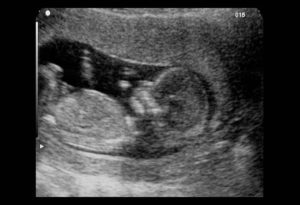

Беременность на 12 неделе — счастливейшее событие для женщины. Угроза раннего выкидыша отступает и плоду больше не угрожает негативное воздействие из внешней среды.

Но несмотря на это, 12 недель — праздник, который подводит к концу первый триместр беременности.

• Акушерская неделя — 12

• Эмбриональная — 10

• День срока — 77-84

Беременность в 12 недель означает, что развитие внутренних органов плода произошло и они продолжают расти дальше. К началу 12 недели размер плода составляет примерно 6 см. За эти 7 дней он подрастет еще на 1-2 см. Все основные ткани и органы малыша развиты, теперь он активно питается через плаценту. Это значит, что самый опасный период его эмбриональной жизни прошел.